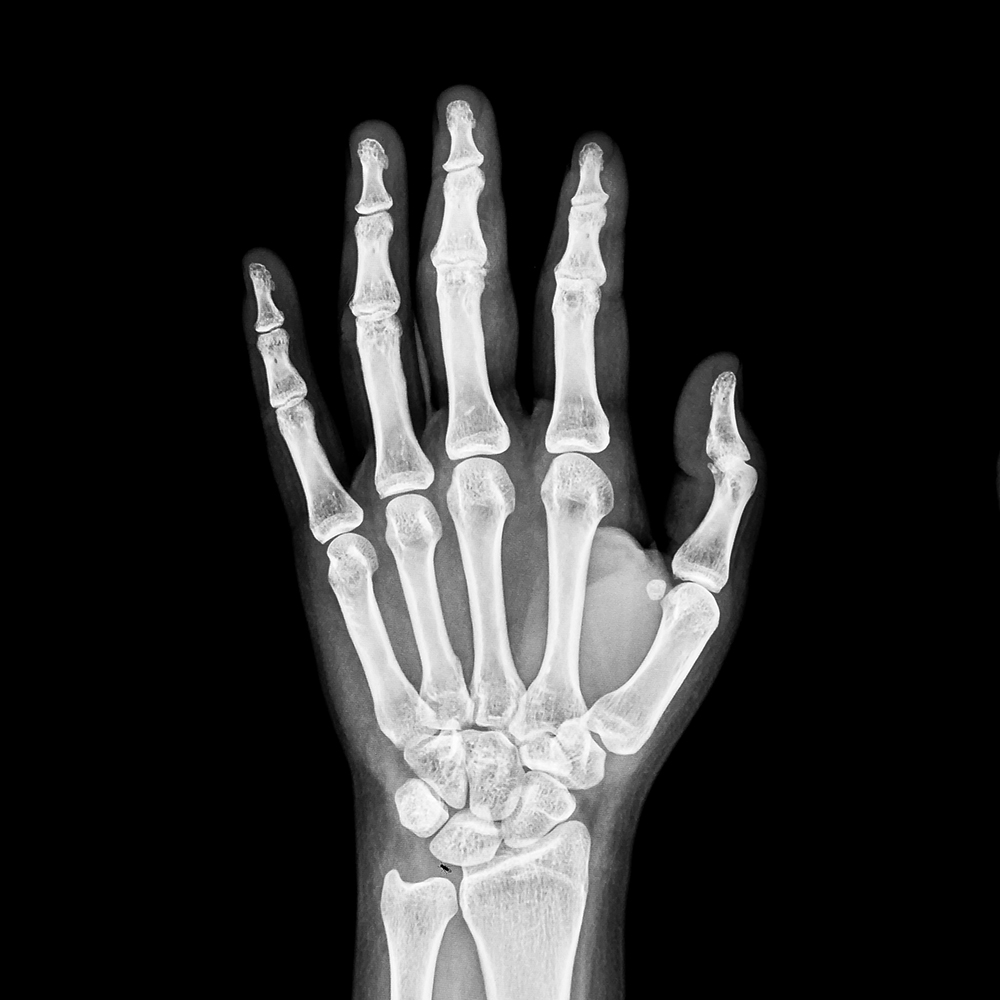

영상의학 검사

서울퍼펙트의 영상의학 검사는 먼저 방사선검사로 확인하며, 다른 질환으로 인한 증상은 아닌지 확인합니다. 손목터널증후군의 경우, 초음파 검사로 정중 신경이 눌려있는지 확인하여 진단합니다.

영상의학검사